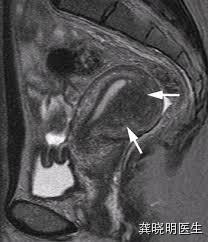

核磁共振检查也会有类似的发现,可以发现肌层有明显的增厚和结构紊乱,在核磁共振上更加明显。